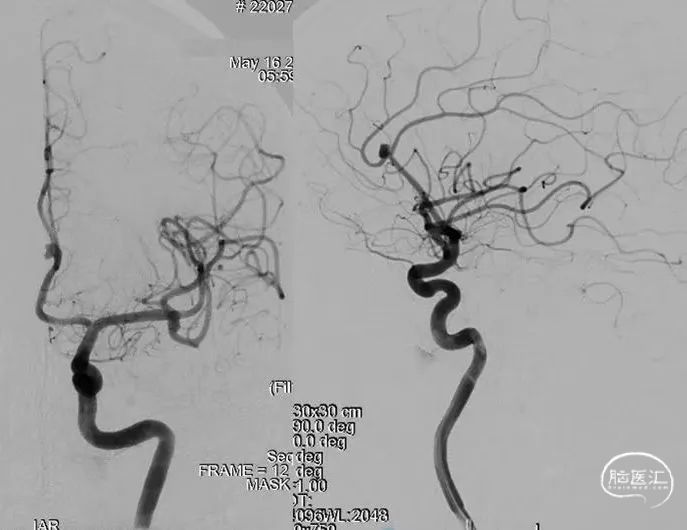

左侧大脑中动脉动脉瘤

动脉瘤部位:

动脉瘤尺寸:

动脉瘤测量:

动脉瘤特点:

手术策略:支架辅助弹簧圈栓塞

术前影像